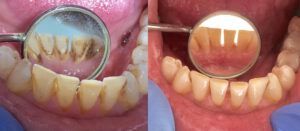

Skaling zębów to profesjonalny zabieg stomatologiczny, którego celem jest dokładne usunięcie kamienia nazębnego, czyli twardych złogów powstałych z zmineralizowanej płytki bakteryjnej. Choć zabieg ten może wydawać się prosty, jego znaczenie dla zdrowia jamy ustnej jest ogromne. Zbagatelizowanie kamienia może prowadzić do chorób przyzębia, utraty zębów, nieświeżego oddechu i próchnicy.

Skaling działa kompleksowo, poprawiając kondycję jamy ustnej i wygląd uśmiechu już po jednej wizycie.